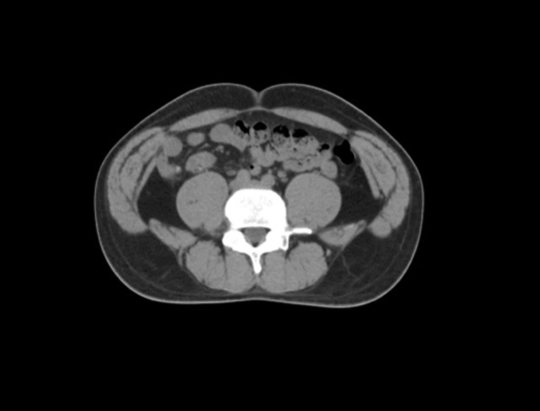

Professor Zhang Zhen, Director of the Radiation Therapy Center of Fudan University Hospital, makes radiotherapy plans for tumor patients

On the one hand, it is imperative to reduce the waiting time and optimize the patient's medical experience. On the other hand, Professor Zhang Zhen  faces many technical bottlenecks in radiotherapy. Radiotherapy is recognized as one of the best treatments for tumors in the world. It can precisely kill cancer cells by avoiding normal tissues, which requires tailor-made treatment for each patient, as well as close coordination of multi-site, multi-medical staff and multi-modal equipment. It also involves six processes: body fixation, simulated positioning, target area outlining, radiotherapy plan creation, plan quality control, image guidance and radiotherapy implementation, and each loop has to be extremely rigorous, which is bound to take a long time. "Is there a way to fundamentally optimize the process so that efficiency and precision can be achieved at the same time?"  Professor Zhang Zhen  has been seeking a solution over the years.

At 9:00 a.m. on March 2, 2021, the first clinical test of this idea was held: for the first time, physicians, physicists and technicians gathered in the control room to perform the first radiotherapy treatment for a rectal cancer patient using All-In-One one-stop radiotherapy technology.CT simulation positioning, intelligent outline and review modification, automatic planning, automatic reset, plan evaluation and review, CT image guidance, treatment and EPID real-time dose monitoring quality control were performed sequentially, and the whole process was completed in 23 minutes in one go, overturning the traditional first radiotherapy process that could only be completed in at least several days. This is a new tumor treatment model created by artificial intelligence technology, which has opened the era of intelligent tumor treatment 2.0.